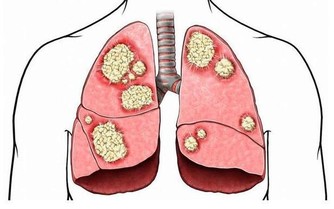

3、一定程度上幫助治療疾病

這一點聽起來很不可思議,但這是有依據的,熱水泡腳可以有效的祛除體內的寒氣,腳底的穴位也得到疏通,在一定程度上,對於治療像是腎臟疾病或者是糖尿病也都是有好處的。